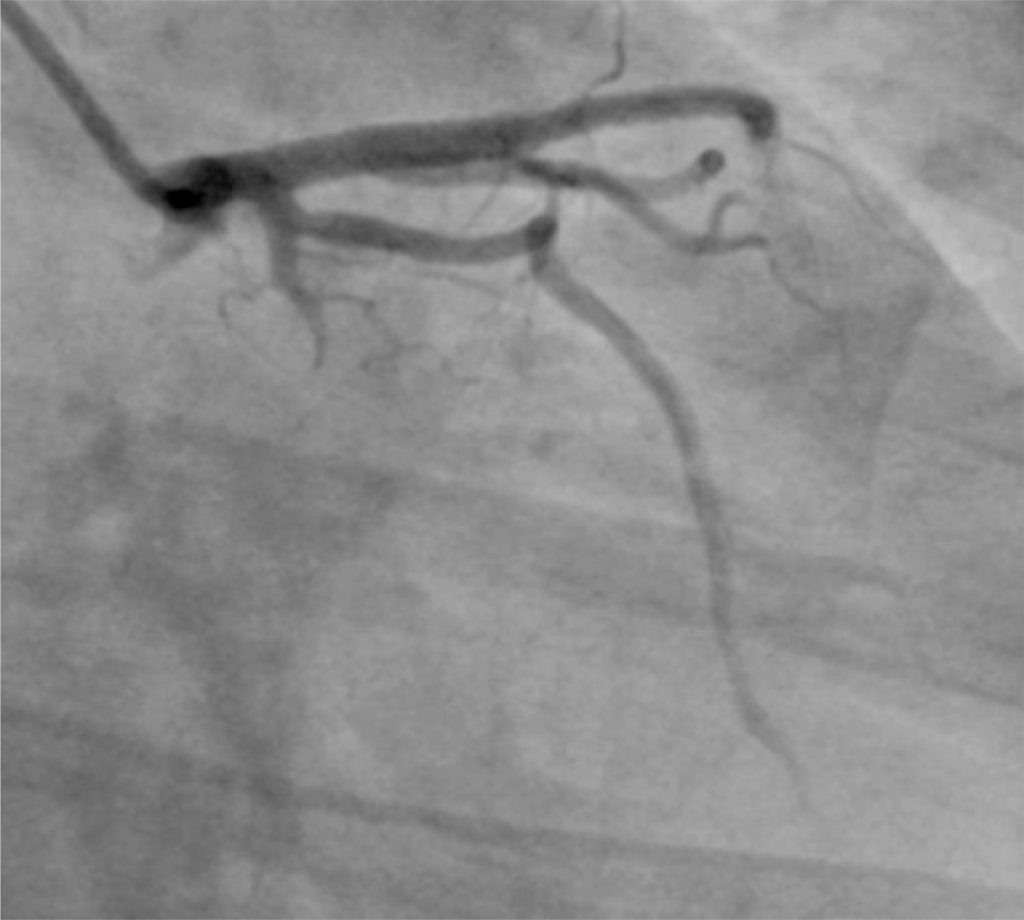

Spontaneous coronary artery dissection is an uncommon cause of myocardial ischemia. Although the first description dates from 1931, its diagnosis is sometimes made late and/or erroneously due to the lack of knowledge of its non-pathognomonic angiographic variations. Additionally, the proper management of this condition is not yet well established. Here we present a rare case of in-hospital recurrence of spontaneous dissection affecting both the left anterior descending and circumflex coronary arteries, with distinct clinical presentations.